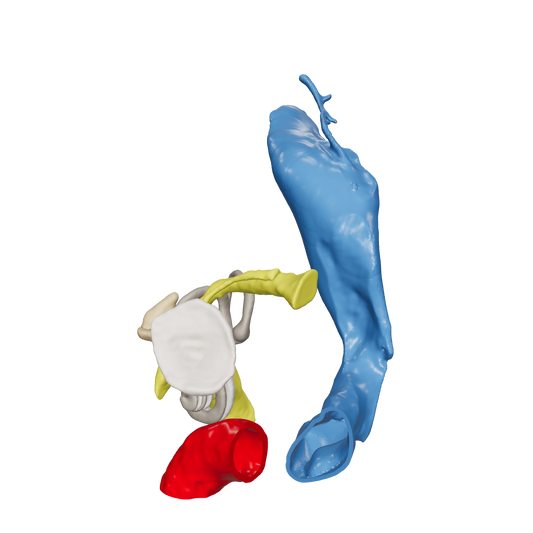

Dissect each one to learn human temporal bone anatomy, hearing and vestibular systems.

*High Contrast Colors* 3D Temporal Bones to Introduce Anatomy (6-pack)

Regular price $402.00 USDRegular priceUnit price per -